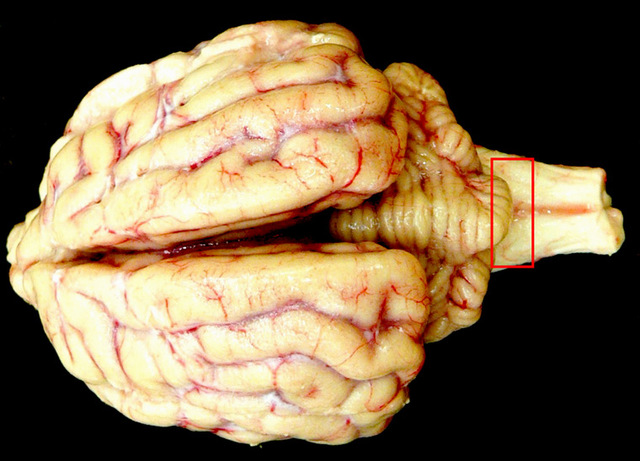

Igor Klatzo fue el primero que observó Placas PAS (+) en cerebros de fallecidos por Kuru, las relacionó con amiloide (El amiloide es una sustancia que se deposita entre las células de distintos tejidos y órganos del cuerpo) y planteó la semejanza de Kuru con Scrapie de oveja y en su contexto general clínico-patológico con enfermedad de Creutzfeldt-Jakob (ECJ).

Se publicó el primer libro sobre ECJ con 150 casos. Ya para entonces estaba clara la imagen histopatológica: cambio espongiforme, ausencia del infiltrado inflamatorio, pérdida neuronal, y placas amiloides.